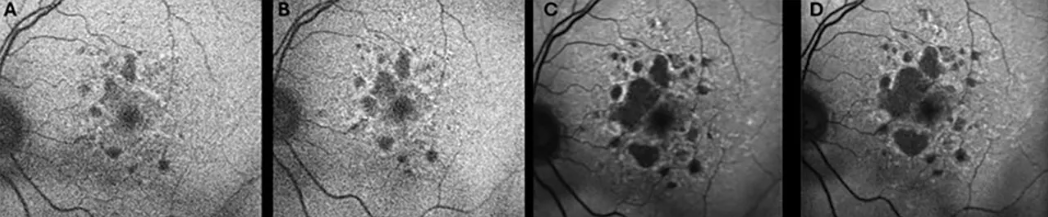

图1   (A) 86岁女性,初诊时存在中心凹下地理萎缩;(B) 6个月、(C) 2年随访时 GA 病灶逐渐扩大;2年随访时开始使用 Syfovre;(D) 7个月内接受5次 Syfovre 注射后,GA 病灶稳定;末次随访视力为20/30

Syfovre 的获批是 GA 治疗的重要里程碑,其依据是两项3期试验(OAKS 和 DERBY)的结果。在 OAKS 研究中,12个月时,与假治疗相比,培克珠单抗每月给药使 GA 病灶生长减缓21%,每两个月给药使生长减缓 16%。在 DERBY 试验中,尽管未达到统计学显著性,但12个月时,培克珠单抗每月给药和每两个月给药分别使 GA 病灶生长减缓12%和11%[10] 。这种 GA 进展的减缓在24个月时持续存在[10]

更令人鼓舞的是,GALE 开放标签扩展研究的结果显示,GA 患者持续接受培克珠单抗治疗3年,疗效逐渐增强。在 GALE 研究中,每月给药使 GA 病灶生长减少35%,每两个月给药减少24%。亚组分析显示,非中心凹 GA 患者(通常视力较好)接受培克珠单抗治疗后,每月给药组的 GA 生长减少42%,每两个月给药组减少24%(与假治疗组相比)[11] 。GALE 扩展研究还首次显示出视觉功能获益,与假治疗组相比,持续36个月每月或每两个月接受治疗的患者,在微视野检查中出现的暗点数量更少[12]